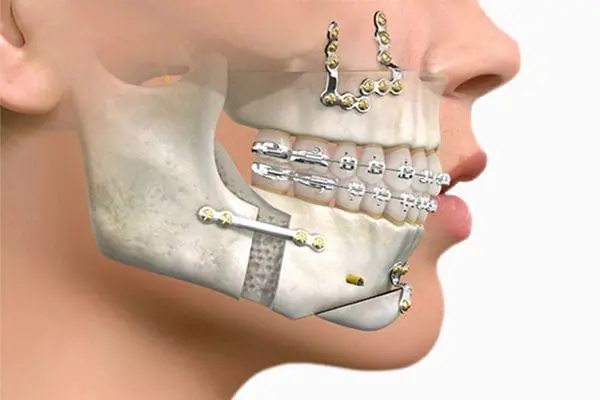

Cirugía Ortognatica:

La cirugía ortognatica es un procedimiento en el cual se puede cambiar la posisiocn de tus huesos, con la finalidad de mejorar, aspectos funcionales y estéticos. Por ejemplo si tienes una mandibula muy grande, o muy pequeña, o bien si tu problema es en el maxilar y se ve una nariz con punta muy abajo, o cuando te ries y se aprecia mucho de la encia.